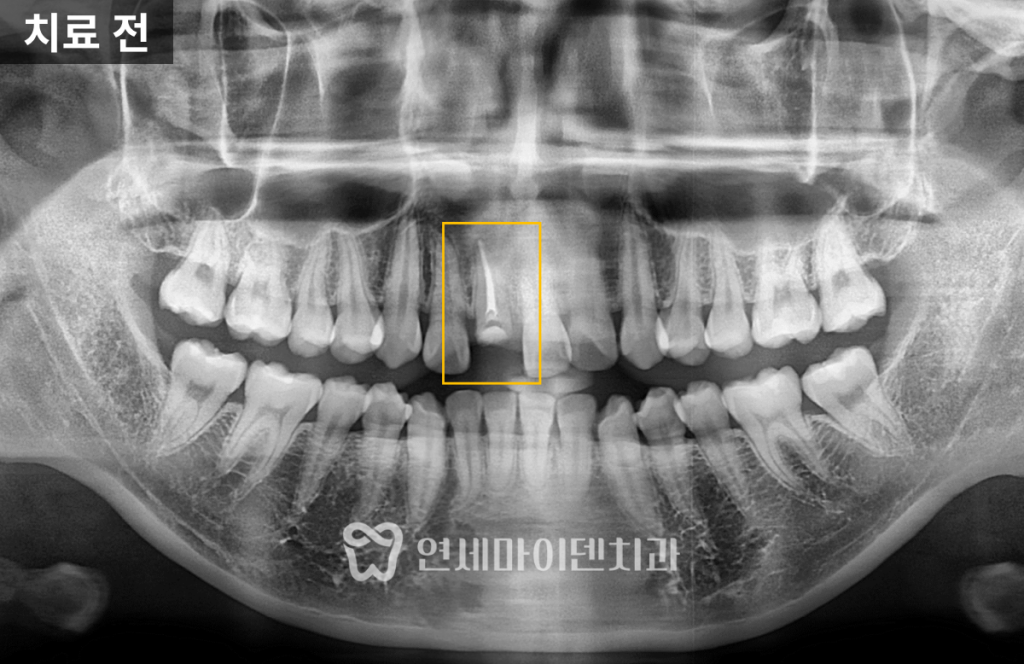

내원 당시 치아는 잇몸 라인과

거의 동일한 위치에서 깨져 있었습니다.

치아가 사라진 자리는 잇몸이 차올라 있고,

잇몸 레벨도 양쪽과 다르게 틀어져 있었습니다.

먼저 임시 재료를 제거하고

치근에 금이 있는지 확인했습니다.

크랙이 있을 경우 살릴 수 없지만,

다행히 이 환자분에게서는 발견되지 않았습니다.